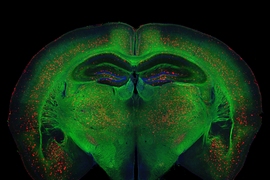

Tsai’s laboratory studies the brain from the genes to higher order cognition such as learning and memory as well as brain disorders such as Alzheimer’s disease. Tsai’s career began with her studies on a protein called cyclin-dependent kinase 5 or Cdk5, which has been found to affect neurodegenerative diseases. She has also studied the cellular machinery that controls the activation and inhibition of genes, also known as epigenetics. In addition, her work on integrating molecular, physiological, and circuit based experimental approaches has provided great insight into the processes of learning and memory. Currently, Tsai’s lab is working to create non-invasive treatments for mice with Alzheimer’s disease.